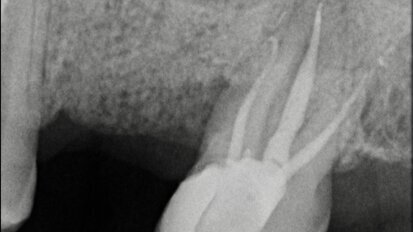

Atraumatic extraction of maxillary first premolar

A 70-year-old female patient visited our clinic owing to a fractured maxillary first molar. Tooth #24 had previously had a large composite restoration that ...